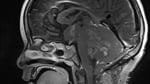

• Medulloblastoma with Intracranial CSF Dissemination

6-year-old female with initial presentation of headache, vomiting and ataxia Ax T2 - 1:06 DWI - 1:48 ADC - 4:32 AX MPRAGE - 5:54 Cor MPRAGE - 8:56 AX T1 Post - 12:15 Sag T1 Post - 12:57